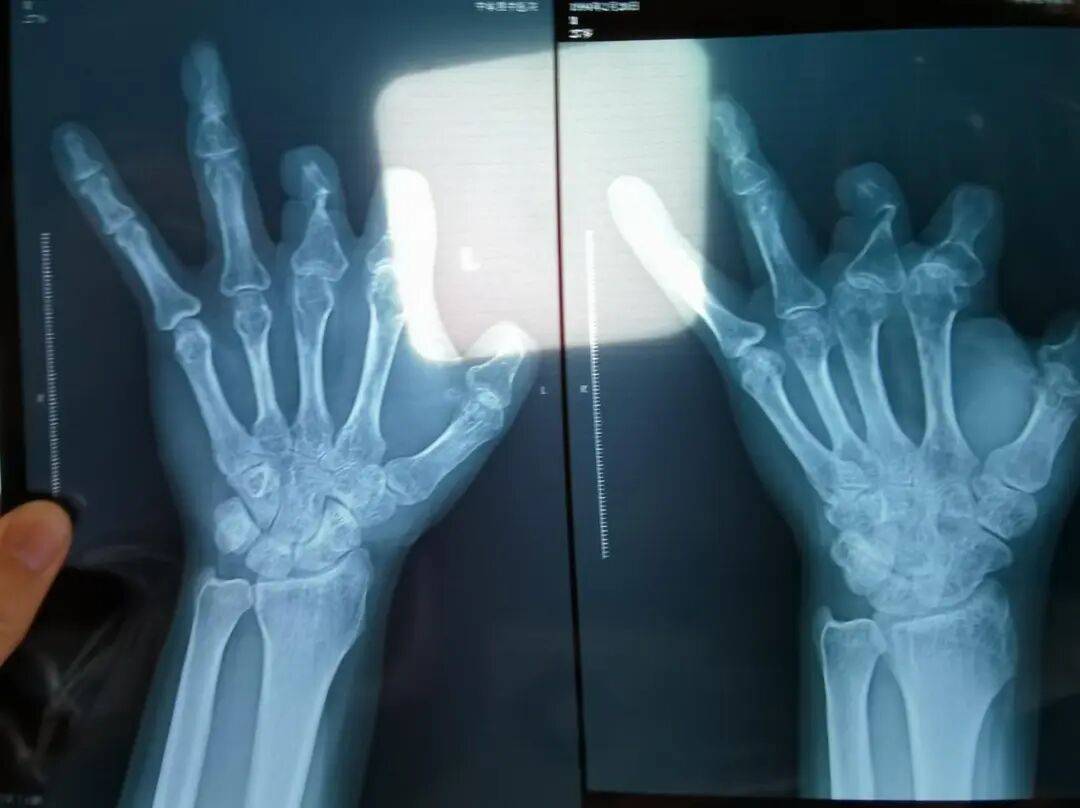

▲患者王海森左手拇指关节以上部位被电锯切断,收费单显示术中使用了微血管吻合装置,但X光片中未显示该器械。新京报记者 程亚龙 摄

彭先生称,因为他的手术并不成功,术后他委托律师欲将郑大一附院诉至法庭。在律师的指导下,他到医院拍摄了X光片,偶然发现术中使用的6个吻合装置,都“消失”在了血管内。

该产品的代理商曾向新京报记者证实,微血管吻合装置为植入型医疗器材,患者拍摄X光片时会有显示。新京报记者获取了一位曾在郑大一附院接受手术、使用了该产品的患者的X光片,其手术部位可见一绿豆大小的光圈。

王海森称,他出院约1年后,有人曾找到他说,这个价格昂贵的进口器材,并没有在手术中使用。当时他没有相信,直到2021年12月,经人提醒,王海森在老家开封尉氏县人民医院拍摄了左手X光片,才确认手术部位的确没有微血管吻合装置。2021年12月底,王海森向郑州市公安局二七分局刑侦大队报案。

▲2021年12月,患者彭先生拍摄的左手X光片,未见收费单据中列出的微血管吻合装置。新京报记者 程亚龙 摄

法院判定,多名被害人证明,其术后接受X光检查,体内均无该装置。94名被害人中,有多名1岁、5岁、6岁不等的儿童因手指创伤接受微血管吻合装置治疗,相比成人血管粗细程度,更能证明该治疗行为的虚假性。在手术过程中,王福建明知多名患者不符合使用微血管吻合装置的条件,又隐瞒未实际使用的事实,将该医疗器械的费用,计入患者的收费清单,致被害人超额支付医疗费用。